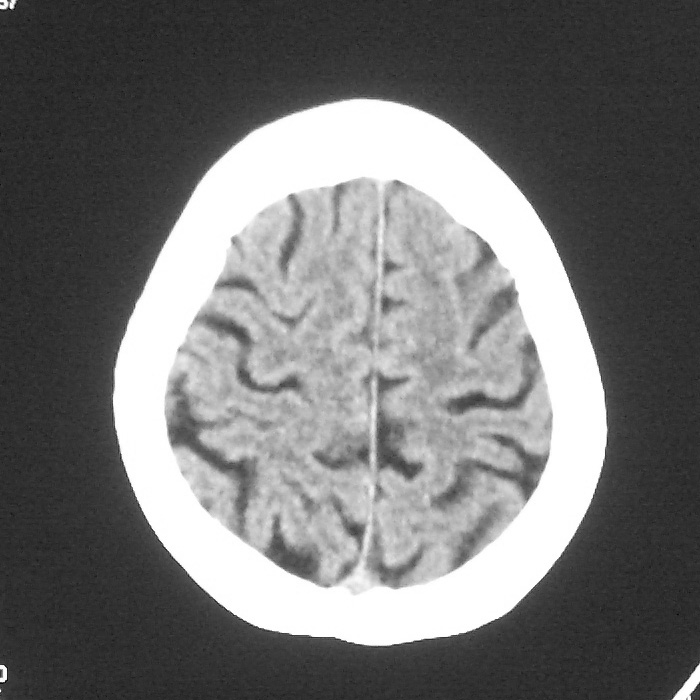

f,70y,口角歪斜、流涎、吐词不清三天

左侧大脑基底节区点状低密度影,边缘清楚,左侧腔梗或软化灶,没什么问题啊?

症状这么明显的话一般不会是单纯面神经麻痹引起的,最好做个mri,如果确实没有问题的话才能考虑面神经麻痹,毕竟这两种病的治疗和预后不一样,这个病人还有脑白质疏松。

左侧半卵圆中心腔梗应当比较明确,右侧基底节好象不明显,不好说,做个mri明确吧

双侧多发腔梗

右侧基底,左侧半卵圆中心腔梗

1、右侧基底,左侧半卵圆中心腔梗。2脑萎缩。

左侧腔隙性梗塞灶,脑萎缩。

左侧基底节区示点状低密度灶,边界清楚,密度均匀,余所示无著变。

意见:腔隙性脑梗塞(左基底节区)

各位老师,报告这么写可以吗?右侧我没有看出来。

左侧半卵圆中心,右侧基底节腔梗。再加个脑萎缩吧

双侧多发腔梗 脑萎缩